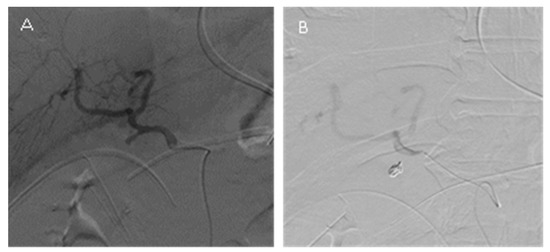

2.2. TAE Procedure